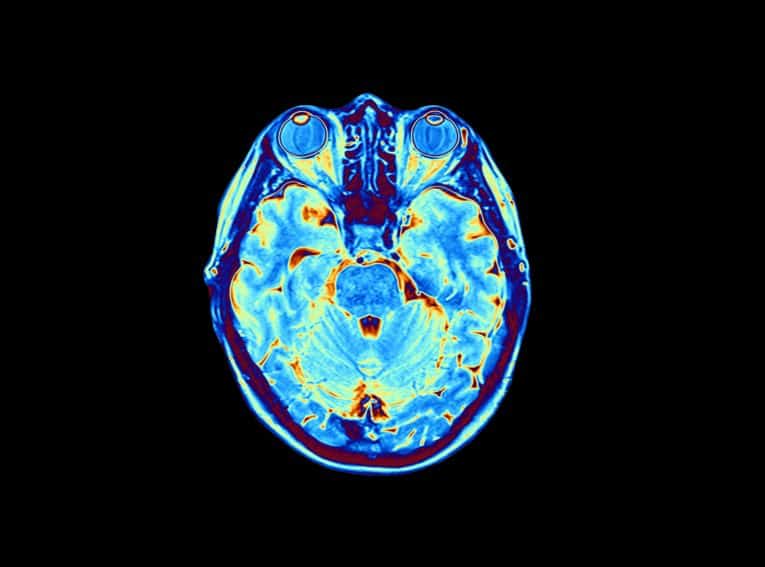

In addition to X-rays of the area to determine the precise location and severity of the bone fracture, a CT or MRI scan is also necessary to determine whether soft tissue has been damaged as well. Treatment is predicated on the extent of injury, if any, to the spinal cord, as well as on the nature of the cervical fracture.